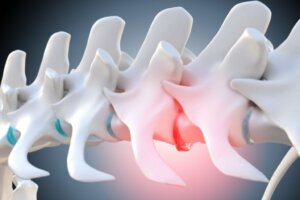

Köpeklerde ağrı son 3 lomber vertebrada (L5-L6-L7) ve pelvisi omurgaya bağlayan sakrumda bulunur. Bel ağrısı kemikleri etkilemesinin yanı sıra bölgedeki kasların çalışmasını artırarak lokomotor düzeyde ağrı ve sertliğe neden olur.

Bu, vücudun iltihaplanma sürecini bir savunma yöntemi olarak harekete geçiren ağrı mekanizmasının kendisinden kaynaklanır. Buna karşılık, bu kas iltihabı, sıkışmaya, hatta omurga çıkıntılarına ve sinir yollarına baskı yaparak fıtıklaşmış disklere neden olur.